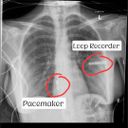

After a long, painful, and lonely 2 weeks in the hospital, I was finally discharged. I was ultimately diagnosed with heart failure, stress induced cardiomyopathy and a rare life-threatening heart condition called Long QT syndrome (LQTS). My most recent diagnosis are PoTs; Postural orthostatic tachycardia syndrome and Addisons disease.